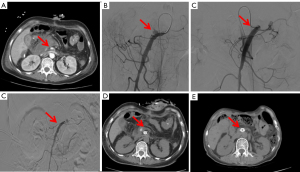

After pancreatic surgery, a pseudoaneurysm in patients was confirmed by CTA. The pancreatic surgeon and interventional surgeon jointly decided to treat the hemorrhage through intravascular intervention. The type of interventional treatment (coil embolization or covered stent placement) was determined by the interventional surgeon depending on the location of the pseudoaneurysm. The clinical course is shown in Figure 1.

Covered stent implantation

For vessels larger than 4 mm in diameter that had inconspicuous tortuosity and supplied vital organs, covered stents were placed. The lesion artery diameter and length were first measured to determine the stent size. If the patient had arterial spasm, preoperative CT was performed to assess the stent size to avoid intimal leakage in type I vessels. The stent covered the proximal and distal ends of the vessel rupture by 1 cm, and other arteries and branches were kept as patent as possible. The diameter of the covered stent was generally 1–2 mm larger than that of the artery. A Mach1 8F guiding catheter (Boston Scientific, Marlborough, MA, USA)—used for a covered stent with a diameter of 5–6 mm—or a Check-Flo 7F long sheath (Cook Medical, Bloomington, IN, USA)—used for a covered stent with a diameter of 7–8 mm—was advanced through the guidewire and pushed to the proximal end of the affected artery. Angiography was performed to confirm the position and ensure no branch occlusion. A 0.018-in guidewire (V-18; Boston Scientific) was used to pass distally to the target artery, and the Viabahn covered stent system (W. L. Gore & Associates, Newark, DE, USA) was placed via a 0.018-in guidewire exchange. Covered stents were 25 or 50 mm in length and ranged from 5 to 8 mm in diameter. Repeat angiography was performed to confirm the exclusion of a pseudoaneurysm (Figure 2). After stent implantation, low-molecular-weight heparin anticoagulant therapy (0.4 mL/4,100 IU; S.C. Q12H) was generally started when the patient’s blood pressure and hemoglobin level became stable. Long-term oral aspirin [100 mg per os (PO) daily] and clopidogrel (75 mg PO daily) antiplatelet therapy was implemented in all surviving patients.

25 mm covered stent was implanted at the lesion site. (D) The contrast catheter was withdrawn to the starting point of the superior mesenteric artery. Re-contrast imaging showed that the stent was unobstructed, and no contrast agent overflow was observed. A follow-up CT scan showed that the covered stent was in place, and there was no narrowing 1 month (E) or 6 months (F) after the implantation of the covered stent. The red arrows respectively represent the positions of pseudoaneurysm and covered stent. CT, computed tomography; CTA, computed tomography angiography.

Coil embolization

Embolization was applied to treat vessels with a small diameter (typically <4 mm), those with a course too tortuous or angular, and those not supplying blood to vital organs. Furthermore, for the bleeding in small arterial branches or vascular stumps that could be treated with covered stents, coil embolization was applied. A microcatheter (STC18; Boston Scientific) was placed in the lumen of the pseudoaneurysm, and contrast agent extravasation was observed on angiography. Microcoils (IDC; Boston Scientific) were used to embolize the inflow and outflow paths of the parent artery. Repeat angiography after embolization showed no extravasation of contrast medium (Figure 3).